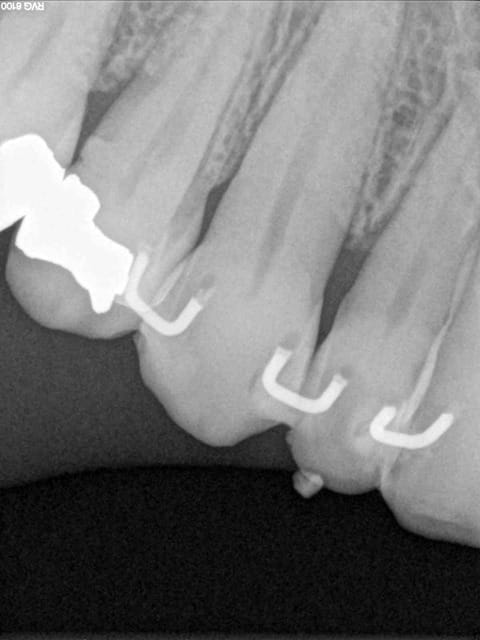

Les attelles d'Abjean j'en pose chaque semaine (ou presque), l'avantage ENOOOOORME par rapport à un "jonc noyé" c'est la rétention 3D que tu n'as pas avec le jonc!

et le délabrement est bcp moindre, en plus quand une attelle lache tu la changes, et pas tout le bastringue!

les miennes tiennent plus de 10 ans...

J'aime beaucoup mon "bridge provisoire" suite à la luxation de la 31 avec fracture de l'apex...^^ elle a tenu 8 ans.

En attendant, ce type de contention transitoire pendant une phase de guérison parodontale après TT ortho (suite aux migrations dentaires) est idéale à mon avis.

3) tu fais une gorge horizontale reliant les 2 points de contact jusqu'à la dentine (prof 1 mm) fraise HL 008

4) un léger avant trou à la fraise boule 008 aux extrémités de la gorge (komet H 009)

5) forage basse vitesse prof 1 à 2 mm les puits doivent être le plus parallèle possible (dans le tiers proximal de la dent à distance raisonnable de la pulpe ;-)

6) confection de l'attelle grâce à une pince à bec plat fine modifiée qui te permet de faire toutes les tailles d'entre-axe

7) essayage et puis souvent réessayage et scellement ou collage si tu en as.

C'est comme cela que Le Pr José Abjean nous l'a appris...à la fac.

C'est joli, mais je trouve que sur les radio, les trous sont plus prodonds que la contention et je trouve cela invasif vs fil ou contention classique. Pour quelques cas bien précis, ok, mais pas trop fréquente l'indication non ?

Ben si en fait, c'est la seule:

1 a être discontinue (donc refaisable sans tt déposer encore une fois)

2 a avoir une rétention axiale, vestibulo palatine, et disto mésiale (3 axes)

3 assez facile à mettre en oeuvre (par rapport à la manipulation d'un long fil que tu colles d'un bout qu'il faut tenir pour ne pas qu'il bouge :(....

4 délabrement moins important et risque de fracture de la dent bcp moindre (bord incisal par exemple)

5 résultat immédiat esthétique et absence d'interférences occlusales car entièrement incluse dans les puits et sillons réalisés.

Ca dépanne super bien dans le cas de la luxation en urgence en attendant la conjointe.